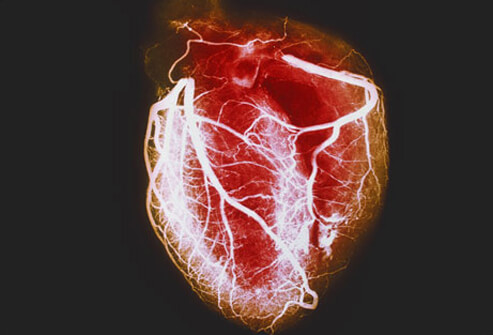

Estudios coronarios en la cardiopatía isquémica estable: ¿TC o cateterismo?

Este estudio no encontró diferencia entre mujeres y varones en el beneficio del uso de la tomografía computarizada (TC) en lugar de la angiografía coronaria invasiva como prueba diagnóstica inicial para el manejo del dolor torácico estable en pacientes con una probabilidad previa a la prueba intermedia de enfermedad arterial coronaria. La TC inicial se asoció con menos complicaciones importantes relacionadas con el procedimiento en las mujeres y una frecuencia más baja del compuesto MACE expandido en los hombres.British Medical Journal, 19 de octubre de 2022.